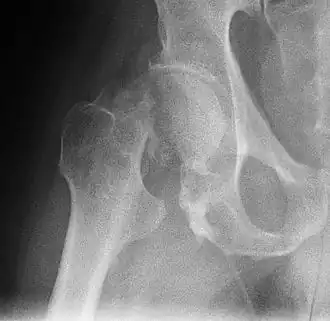

Une fracture de l'extrémité supérieure du fémur (ou fracture de l'extrémité proximale du fémur), appelée couramment « fracture de la hanche » ou fracture du col du fémur, désigne une fracture du fémur localisée au niveau de son épiphyse supérieure.

L'extrémité supérieure du fémur comprend le grand trochanter, le petit trochanter, le col du fémur et la tête du fémur. Deux tiers des fractures passent dans le massif des trochanters, un tiers seulement intéresse vraiment le col du fémur.

On classifie les fractures du col du fémur selon la classification de Garden[6]:

- Garden I : fracture engrenée en valgus

- Garden II : fracture sans déplacement

- Garden III : fracture en varus, avec déplacement

- Garden IV : fracture en varus, avec déplacement important et désolidarisation [7]

Le diagnostic est confirmé par des radiographies de la hanche de face et de profil.

Il existe plusieurs classifications des fractures selon la localisation et selon le déplacement.

Elles se repèrent par la classique triple déformation du membre inférieur qui est en adduction, raccourcie et en rotation externe et on la confirme par un bilan radiographique (bassin et hanche) où l’on peut distinguer :

- deux types via la classification de Pauwels selon l’orientation du trait fracturaire : vertical instable et horizontal stable.

- quatre stades via la classification de Garden selon l’orientation des travées qui bougent avec le déplacement de la tête fémorale : si elles se déplacent vers le haut on parle de valgus (1), ouvrant l’angle cervico diaphysaire ; alors que vers le bas, fermant l’angle cervico diaphysaire on parle de varus (3-4).